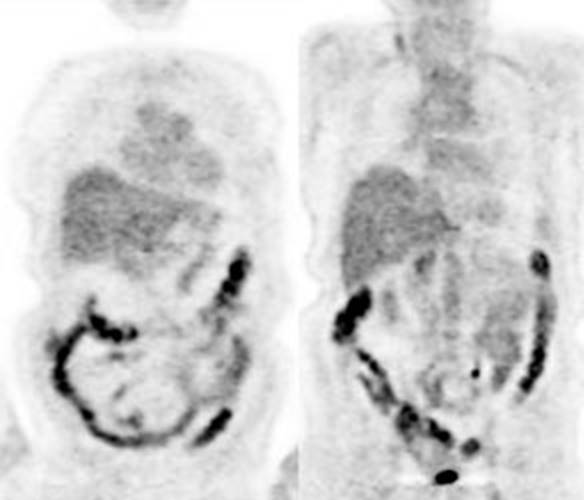

Figure 15 - Diffuse large bowel

activity: Diffuse

increased colonic FDG uptake was seen in this asymptomatic patient. Diffuse

uptake is usually not associated with underlying bowel abnormality.